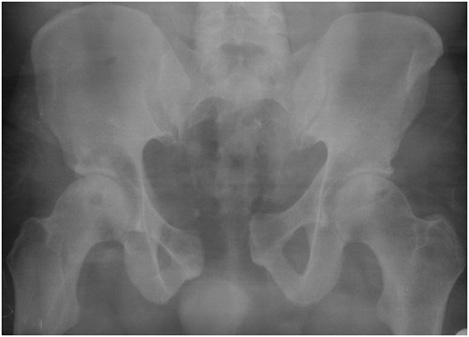

Fig1. - 'Open book' fracture of the pelvis.

Fig1. - Treated with open reduction and internal fixation.